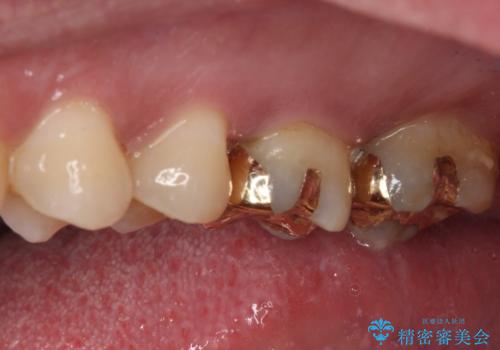

- 銀歯の周りの歯が欠けてしまい、気になるとのことで来院された患者様です。

元々の銀歯も大きく装着されていたため、虫歯治療後はセラミッククラウンにて補綴することとしました。